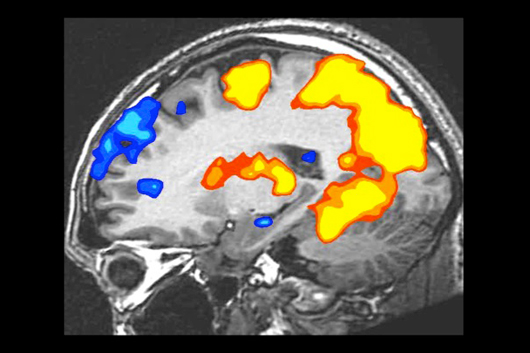

次の写真はスタンフォード大学の研究による

「ゲームをする人の脳内画像」です。

色がついているのが、

血流の活性化している部分です。

詳しく調べると、ゲームをしている人々の脳内は、

特に2つの部分が活性化していました。

1つめは、

「モチベーションを感じる部分」です。

人は、この部分が活性化すると、

より熱心に目標達成を目指すようになります。

努力が辛くなくなり、諦めなくなります。

「もっと、もっと!」とゴールを目指します。

だからゲームをしている人たちは、

「まだやめたくない」という感情になるわけです。

活性化する2つめは

「学習能力を高める部分」です。

この部分が活性化すると、注意力が高まり、

一度により多くの情報を処理できるようになります。

失敗しても、たくさんのことを学べます。

進むにつれてだんだん難易度が高くなるようなゲームは、

特にこの部分を活性化させてくれます。